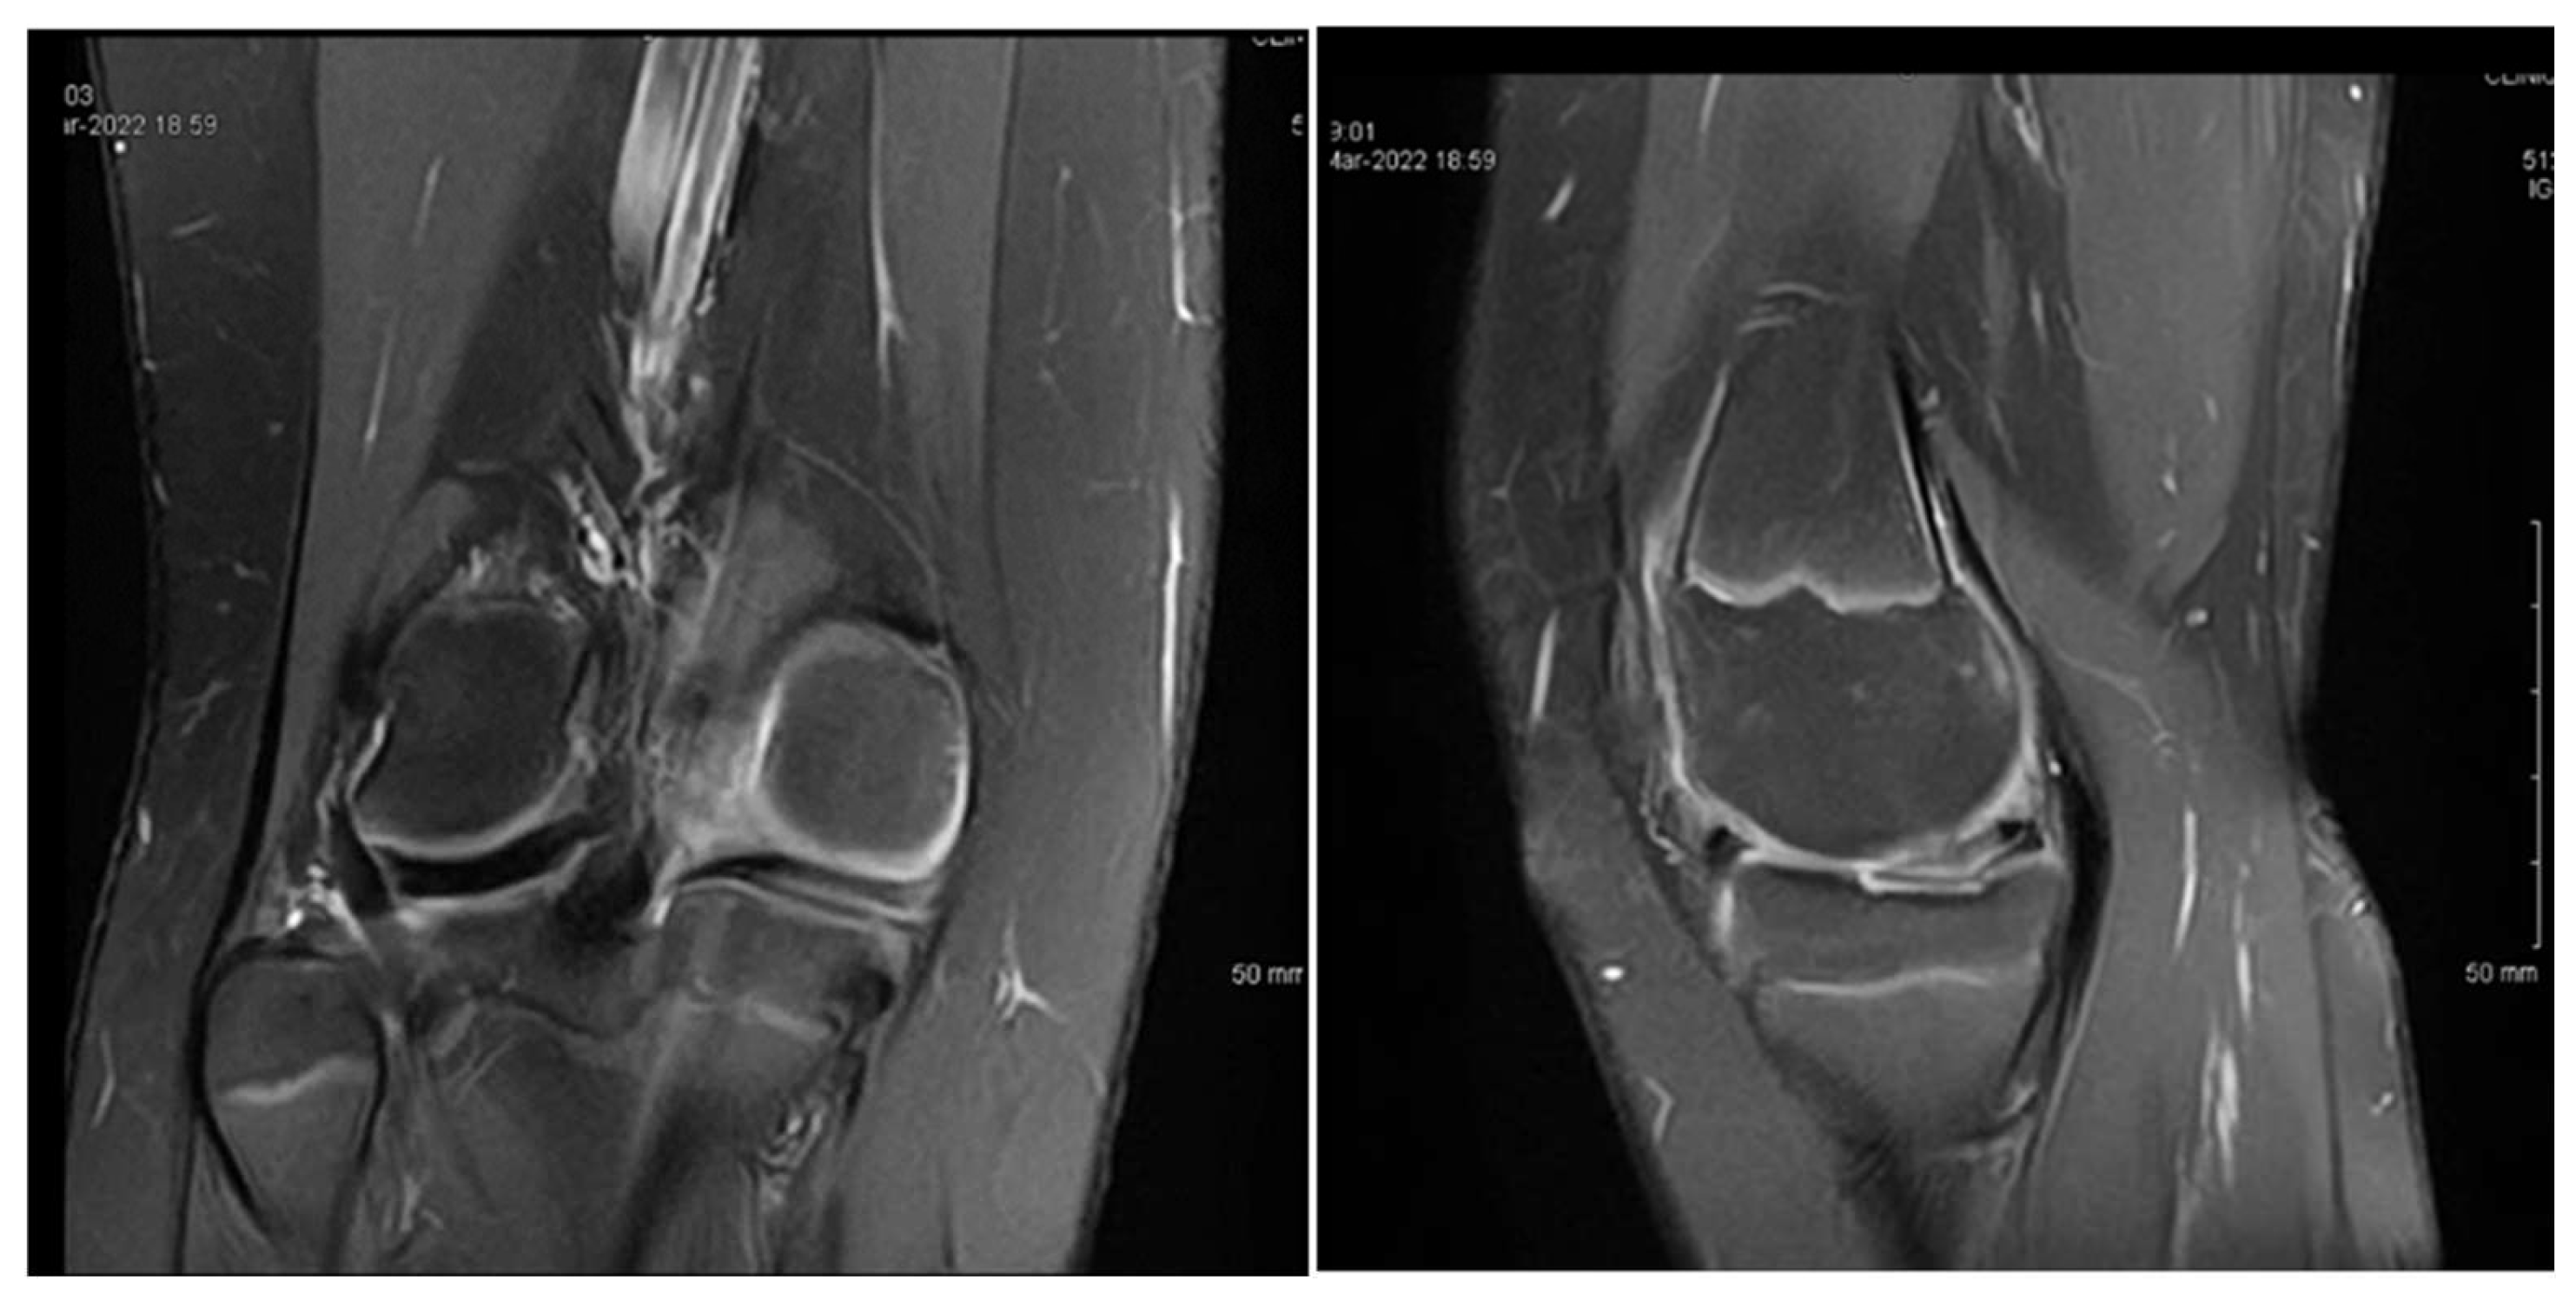

3.1. Case 1—P.E.

3.2. Case 2—S.C.S.

3.3. Case 3—G.L.

| P.E. | 12 | Bilateral (symptomatic right) | Chronic pain, effusion, normal ROM | None | 3 surgeries: partial meniscectomy (12 years), suture for horizontal tear (13 years), suture for radial tear (14 years) | 1 year after third surgery: symptom-free, resumed school sports |

| S.C.S. | 13 | Left | Pain, occasional locking, normal ROM | Dancing | 1 surgery: partial meniscectomy and suture for horizontal tear (13) | 6 months: symptom-free, full ROM, resumed dancing |

| G.L. | 14 | Bilateral (symptomatic right) | Pain, medial tenderness, normal ROM | Basketball | 1 surgery: partial meniscectomy and suture for horizontal tear (14) | 6 months: symptom-free, full ROM |